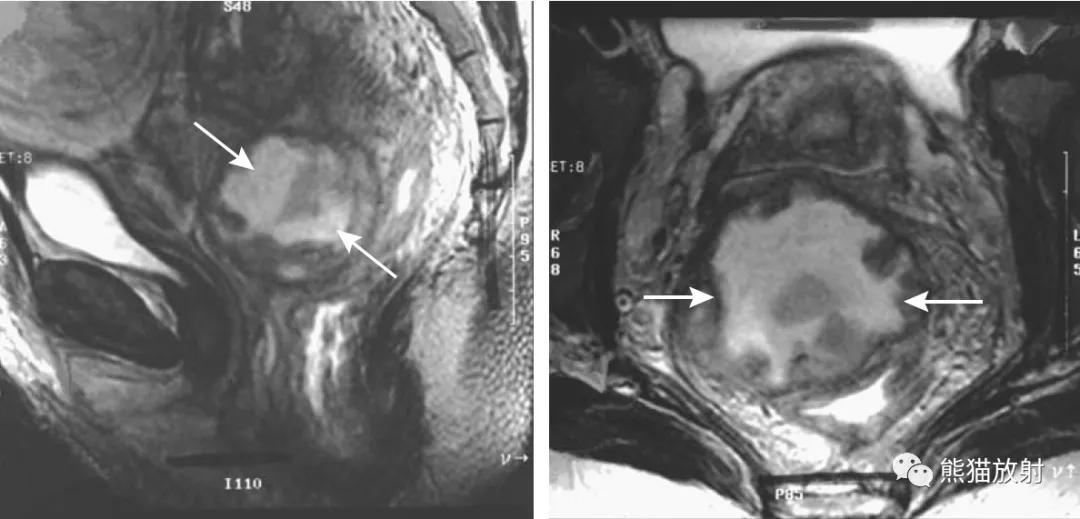

直肠子宫内膜异位(箭头)。局灶性的、波纹状的直肠前壁受累是典型表现。

子宫内膜异位症累及子宫直肠陷凹。矢状(A)和横断(B)的T2WI图像显示子宫和直肠之间可见不均质肿瘤(箭头),显示直肠前壁是如何经常被累及。

直肠周围脓肿(易误诊为直肠癌)。4个月前因增生行前列腺切除术,出现便秘。盆腔CT显示直肠病变并管腔变窄(箭头)。T1和T2加权图像显示直肠壁增厚和周围充满液体的结构(箭),提示脓肿或坏死性肿瘤。